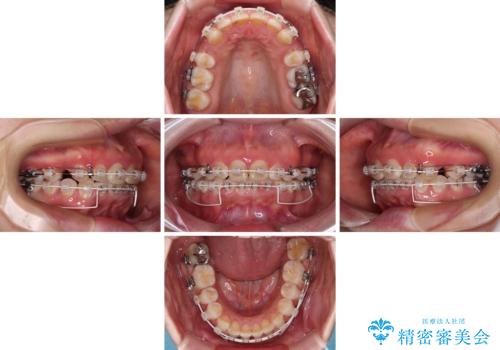

出っ歯を治したい ワイヤー装置での抜歯矯正

上顎歯列全体が前方に飛び出している印象であったので、上顎左右の第一小臼歯2本を抜歯し、ワイヤー装置にて抜歯矯正を行うこととしました。

骨格的に上顎が前方にあり、上顎のみの抜歯矯正のため、期間はかかることが予想されましたが、スムーズに移動してくれたおかげで、2年弱の短期間で終えることができました。